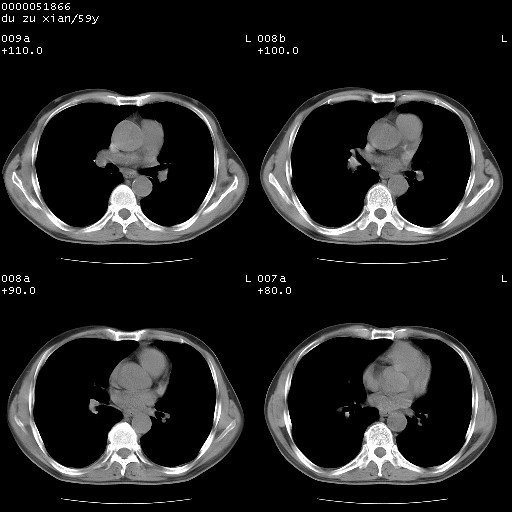

以下是引用宇宙ct在2008-8-25 23:21:00的发言:[br]右肺周围性肺癌并肋骨转移,纵隔淋巴结转移。

以下是引用zsl6918在2008-8-25 22:40:00的发言:[br]右肺周围性肺癌并肋骨转移,纵隔淋巴结转移。

以下是引用zy_zj在2008-8-26 15:24:00的发言:[br]单从病变本身,我倾向良性炎性病变,但肋骨转移了,所以说是考虑右肺周围性肺癌并肋骨、纵隔淋巴结转移可能性大。